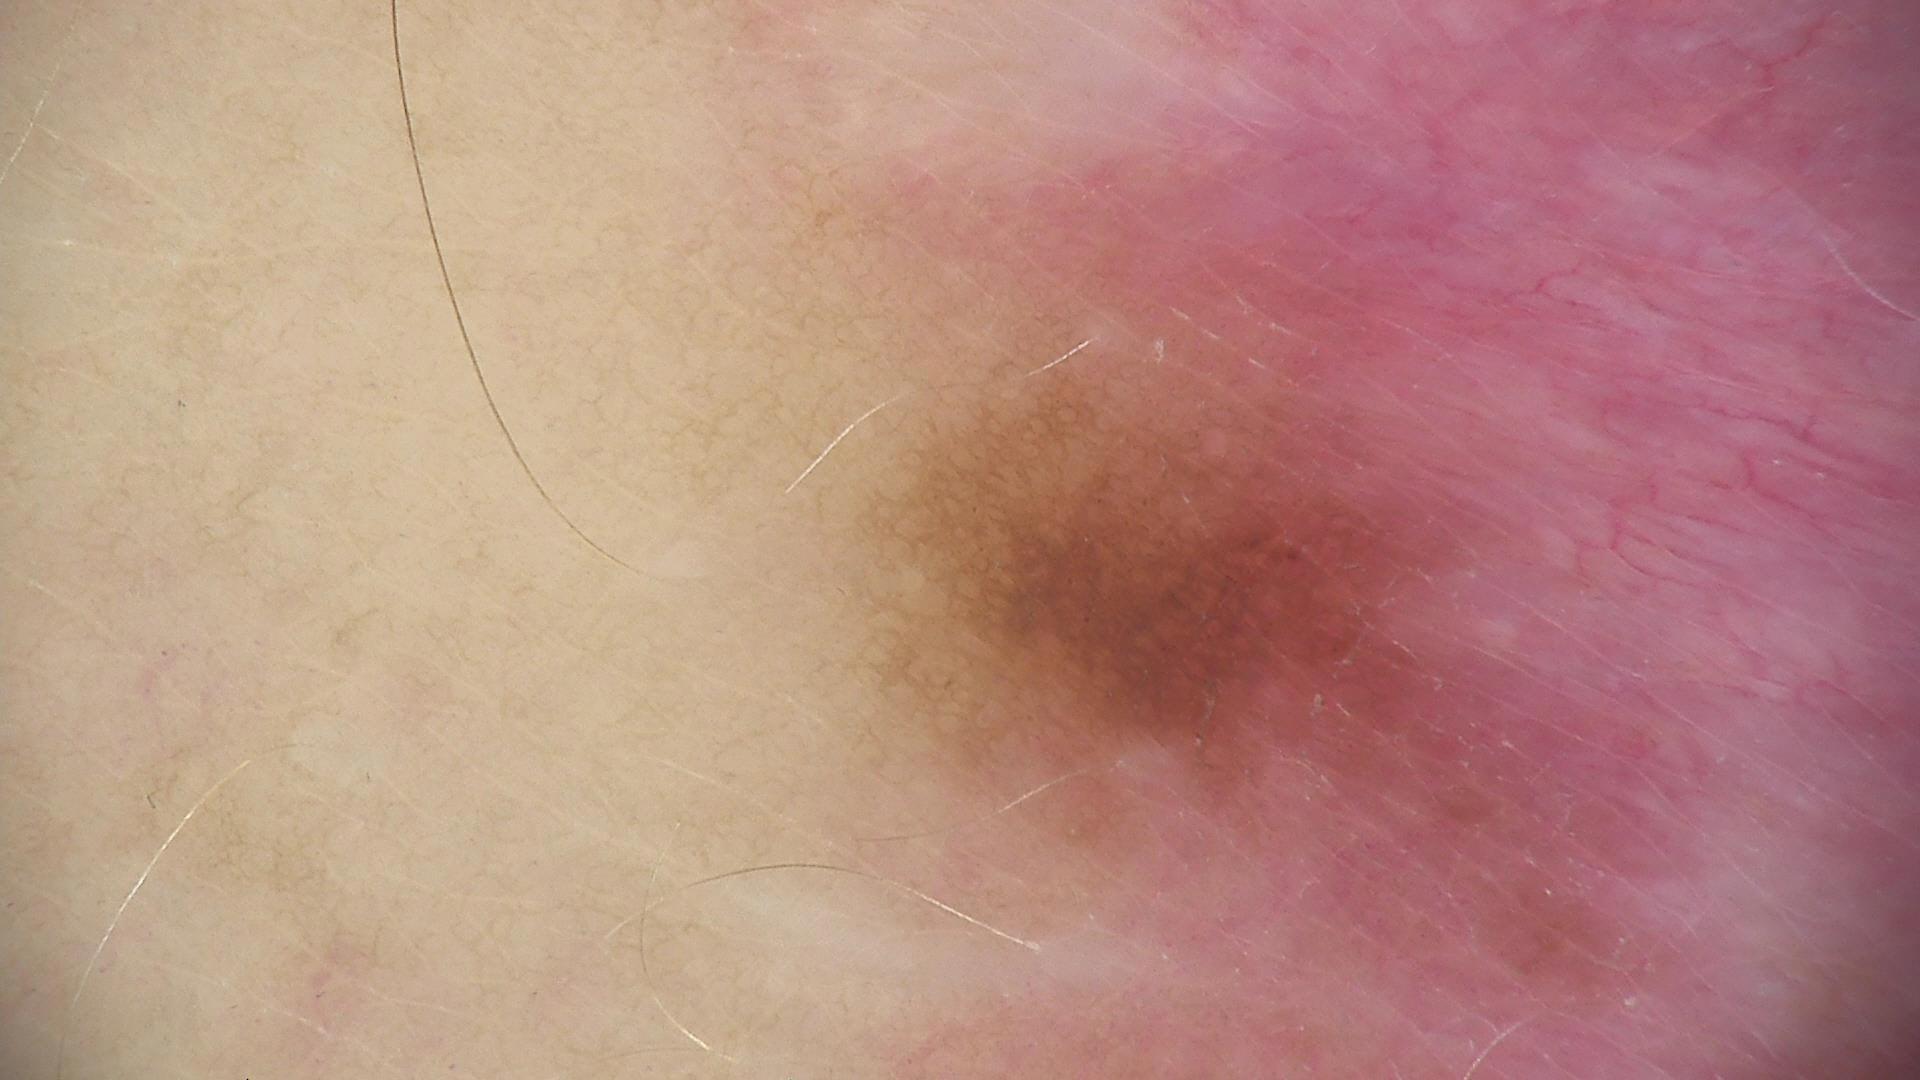

Skin lesion datasets provide essential information for understanding various skin conditions and developing effective diagnostic tools. They aid the artificial intelligence-based early detection of skin cancer, facilitate treatment planning, and contribute to medical education and research. Published large datasets have partially coverage the subclassifications of the skin lesions. This limitation highlights the need for more expansive and varied datasets to reduce false predictions and help improve the failure analysis for skin lesions. This study presents a diverse dataset comprising 12,345 dermatoscopic images with 40 subclasses of skin lesions, collected in Turkiye, which comprises different skin types in the transition zone between Europe and Asia. Each subgroup contains high-resolution images and expert annotations, providing a strong and reliable basis for future research. The detailed analysis of each subgroup provided in this study facilitates targeted research endeavors and enhances the depth of understanding regarding the skin lesions. This dataset distinguishes itself through a diverse structure with its 5 super classes, 15 main classes, 40 subclasses and 12,345 high-resolution dermatoscopic images.

Yilmaz, A., Yasar, S.P., Gencoglan, G. et al. DERM12345: A Large, Multisource Dermatoscopic Skin Lesion Dataset with 40 Subclasses. Sci Data 11, 1302 (2024). https://doi.org/10.1038/s41597-024-04104-3